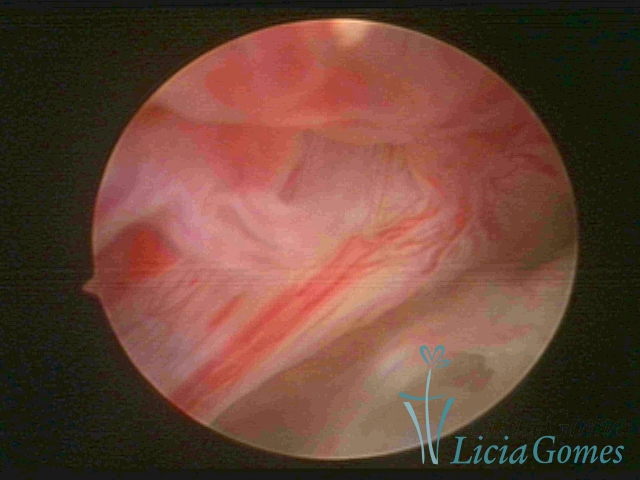

• SINÉQUIA TIPO FIBROMUSCULAR